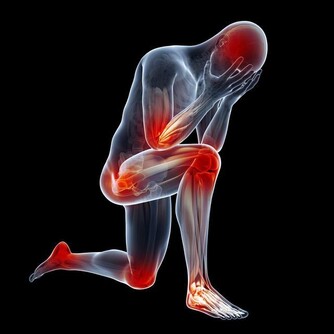

5、全身表現:

身體乏力、容易疲勞是最常見的全身表現。